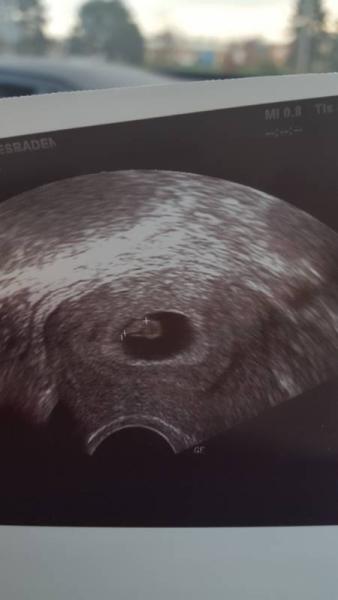

Ich war gestern das erste mal beim Ultraschall bei 6+5

Dem Krümel geht es gut und ist 6.3 mm groß

Das Herz hat ordentlich geschlagen, ich habe noch nie was schöneres gesehen